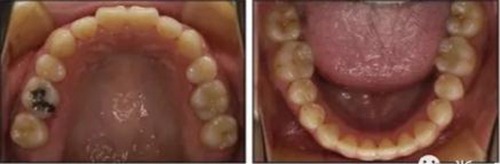

治療后數(shù)據(jù)提示治療目標(biāo)達(dá)成。面相結(jié)果提示微笑及側(cè)貌得到改善(圖6)。達(dá)到了安氏I類(lèi)尖牙關(guān)系和安氏II類(lèi)磨牙關(guān)系,形成尖牙保護(hù)合。牙齒中線無(wú)偏斜,達(dá)到理想的覆合覆蓋,Spee曲線得到整平。

治療后全景片提示間隙得到關(guān)閉,除了左下頜第一前磨牙外牙根平行度可,無(wú)明顯骨及牙根吸收。(圖7)